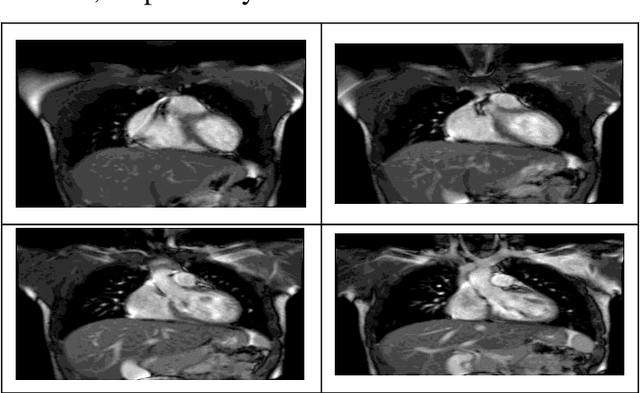

Abstract:Cardiovascular disease is one of the most challenging diseases in middle-aged and older people, which causes high mortality. Coronary artery disease (CAD) is known as a common cardiovascular disease. A standard clinical tool for diagnosing CAD is angiography. The main challenges are dangerous side effects and high angiography costs. Today, the development of artificial intelligence-based methods is a valuable achievement for diagnosing disease. Hence, in this paper, artificial intelligence methods such as neural network (NN), deep neural network (DNN), and Fuzzy C-Means clustering combined with deep neural network (FCM-DNN) are developed for diagnosing CAD on a cardiac magnetic resonance imaging (CMRI) dataset. The original dataset is used in two different approaches. First, the labeled dataset is applied to the NN and DNN to create the NN and DNN models. Second, the labels are removed, and the unlabeled dataset is clustered via the FCM method, and then, the clustered dataset is fed to the DNN to create the FCM-DNN model. By utilizing the second clustering and modeling, the training process is improved, and consequently, the accuracy is increased. As a result, the proposed FCM-DNN model achieves the best performance with a 99.91% accuracy specifying 10 clusters, i.e., 5 clusters for healthy subjects and 5 clusters for sick subjects, through the 10-fold cross-validation technique compared to the NN and DNN models reaching the accuracies of 92.18% and 99.63%, respectively. To the best of our knowledge, no study has been conducted for CAD diagnosis on the CMRI dataset using artificial intelligence methods. The results confirm that the proposed FCM-DNN model can be helpful for scientific and research centers.